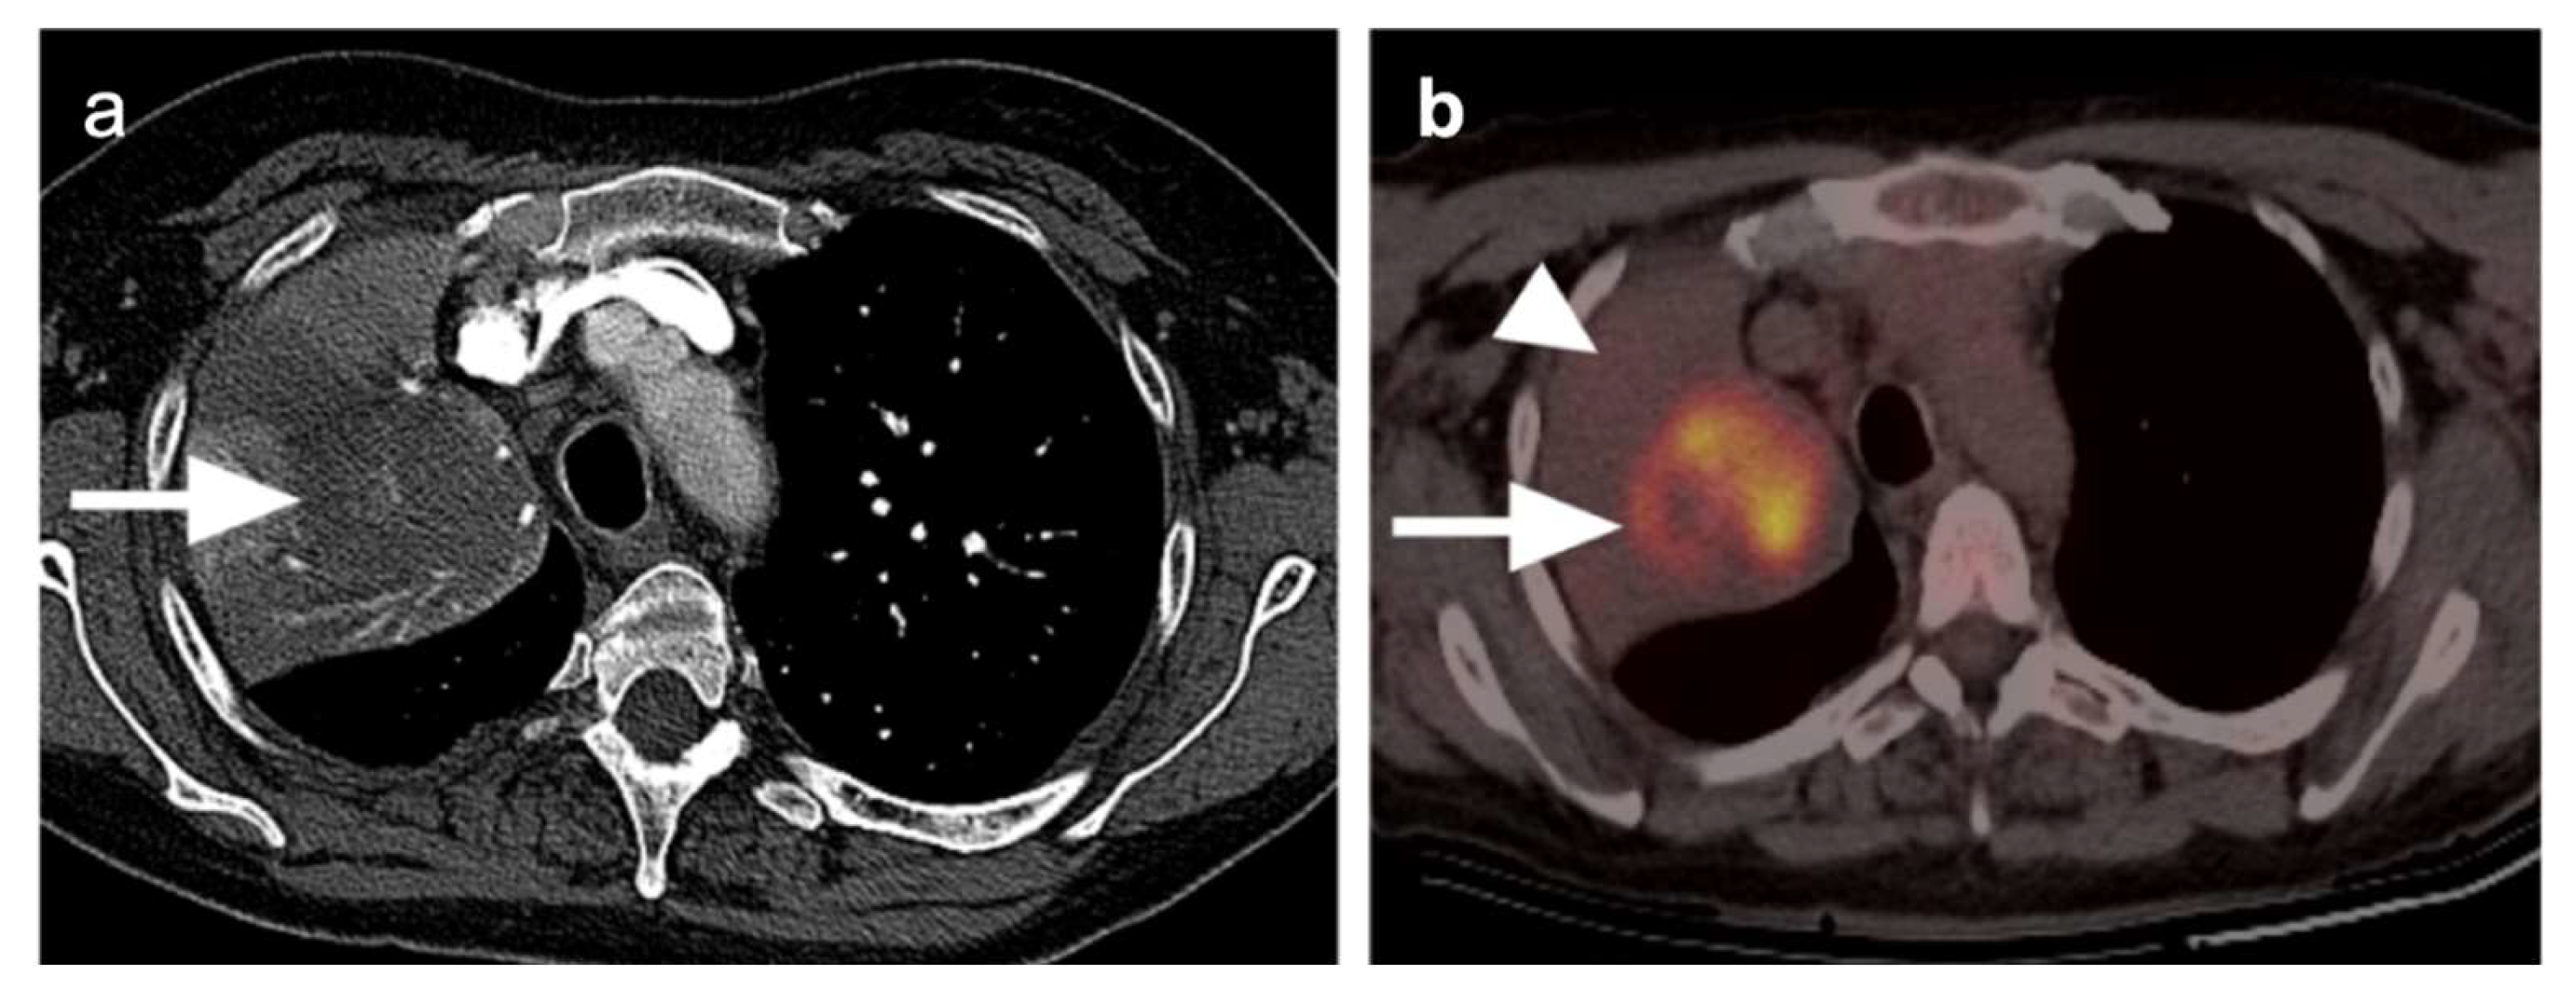

2.4. Small Cell Lung Cancer

Small cell lung cancer (SCLC) is an extremely aggressive tumor type which accounts for about 10–15% of all lung cancer cases [38,39]. It originates from neuroendocrine precursor cells and is characterized by rapid growth and early metastatic potential, with approximately 70% of patients presenting initially with metastases [40]. Up to 10–25% of patients with SCLC have brain metastases at the time of initial diagnosis and an additional 40–50% will develop brain metastases during the course of their disease. Although SCLC is usually chemo-sensitive in the early stages and sensitive to radiation therapy, most patients with SCLC will experience recurrent disease leading to death. Over 95% of patients with SCLC are either current or former smokers [2]. According to the Veterans Administration Lung Group’s criteria, SCLC has been traditionally divided into two stages—a binary system of staging—limited disease and extensive disease [41]. Limited-stage disease SCLC (LD-SCLC) is disease confined to ipsilateral hemithorax, mediastinum (including contralateral mediastinal nodes), and ipsilateral supraclavicular nodal involvement, which can be encompassed within a single radiation field (Figure 11) [42]. Extensive-stage disease SCLC (ED-SCLC) is spread beyond the ipsilateral hemithorax including hematogenous metastatic disease and presence of malignant pleural or pericardial effusion (Figure 12) [39,43]. Standard therapy for patients with LD-SCLC includes chemotherapy in conjunction with radiation therapy. Due to high potential for developing brain metastases in this group of patients, palliative cranial radiation is also indicated to increase overall survival. In ED-SCLC, only systemic chemotherapy is considered, as a palliative treatment, because long-term survival in these patients is rare [43,44]. According to the more recently adopted AJCC (American Joint Commission on Cancer) TNM staging system 8th edition, there is no significant difference between NSCLC and SCLC in the staging system [26]. The NCCN Panel adopted a combined approach for staging SCLC using both the AJCC TNM staging system and the VA scheme for SCLC. In applying the TNM classification to the VA system, the so-called limited-stage SCLC is defined as stage I–III (any T, any N, and M0, respectively), which can be effectively treated with definitive radiation therapy and extensive-stage SCLC is defined as stage IV (any T, any N and M1a/b) or T3–T4, harboring multiple lung nodules or tumor volume that is too large to be encompassed in a tolerable radiation plan/field.

A number of diagnostic modalities have been applied to the staging of SCLC. CT of the chest, CT of the abdomen/pelvis, and MRI of the brain are the most common for staging SCLC, with inclusion of Tc-99m bisphosphonate bone scan in some cases. Multiple studies have evaluated the diagnostic accuracy of FDG PET-CT staging compared to conventional staging in patients with SCLC [45,46,47]. In a prospective study by Fischer et al., the diagnostic performance of FDG PET-CT in correctly diagnosing LD-SCLC and ED-SCLC was 95% and it was higher compared with that of conventional imaging methods with diagnostic accuracy of 85% [47]. The better diagnostic performance of FDG PET-CT in correctly staging LD-SCLC and ED-SCLC was also confirmed by another prospective study by Kishida et al., who found a diagnostic accuracy of 96.6% for FDG PET-CT compared to 91.5% correctly staged as ED-SCLC or LD-SCLC for conventional staging, although this difference was not statistically significant [45]. Few studies have also assessed the change of binary SCLC staging using FDG PET-CT compared to conventional staging (upstaging from LD-SCLC to ED-SCLC or downstaging from ED-SCLC to LD-SCLC), reporting percentages ranging from 5.1 to 21.7% [45]. A recent report supported that whole-body MRI and FDG PET-MRI may offer some advantages over FDG PET-CT and conventional CT in T-staging of the tumor, particularly in determining whether local invasion is present [48].